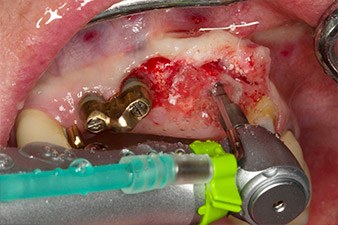

Der Alveolarknochen erweist sich an Position 22 als ausreichend dimensioniert. Die Abbildungen 2 und 4 zeigen die Implantatbett-Aufbereitung, den Gewindeschnitt und die Implantation mit dem Implantmed.

Um den parodontalen Knochenverlust auszugleichen und ein ästhetisches Ergebnis zu erreichen, wird die Implantation mit gesteuerter Knochenregeneration mit xenogenem Ersatzmaterial und einer Kollagenmembran kombiniert (Abb. 5 und 6).

Im Rahmen der Freilegung für die Implantation an Position 23 wird vier Monate später die Implantatstabilität mit dem im Gerät integrierten W&H Osstell ISQ-Modul gemessen (Implantat-Stabilitäts-Quotient).

Dafür wird der zum Implantatsystem passende Messpfosten (SmartPeg) aufgeschraubt und die Sonde in einem Abstand von 3-5 mm von der Stirnseite des Messpfostens positioniert (Abb. 7).